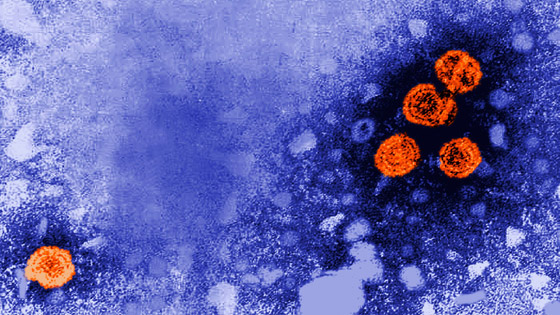

وصل مرض الكبد الغامض الذي أصاب أطفالاً في 12 دولة حول العالم إلى آسيا، بعد تسجيل حالة في اليابان، إذ أعلنت السلطات المحلية عن حالة التهاب الكبد الحاد مجهول المنشأ في اليابان، لدى طفل جاءت نتيجة فحوصاته إيجابية بالفيروس الغدي، وهو سبب محتمل للإصابة يخضع للدراسة على مستوى العالم.

ومن النظريات التي تحقق فيها هيئة الأمن الصحي في المملكة المتحدة، أن قلة التعرض للفيروس الغدي الشائع -الذي عادة ما يسبب اضطرابات في المعدة ونزلات البرد- أثناء جائحة فيروس كورونا، أدت إلى اشتداد حدة المرض بين الأطفال. ومن بين 53 حالة خضعت للفحص في المملكة المتحدة، ظهر على 40 حالة (75%) علامات الإصابة بالفيروس الغدي.